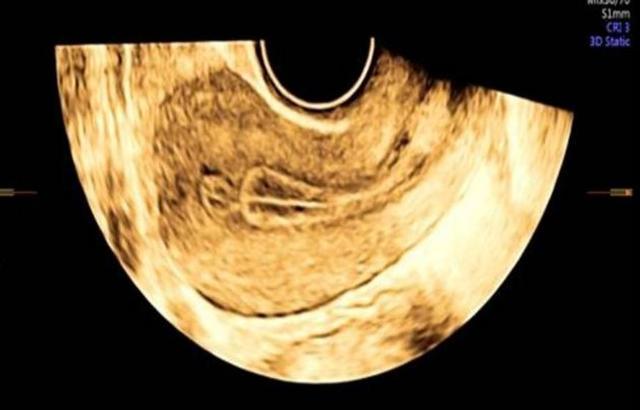

以上是二维超声的图像,而三维成像下的宫腔粘连更加直观。

而在下面这张图我们可以看到:宫腔失去了正常倒三角的形态,下段宫腔因为粘连导致缩窄呈窄桶状。